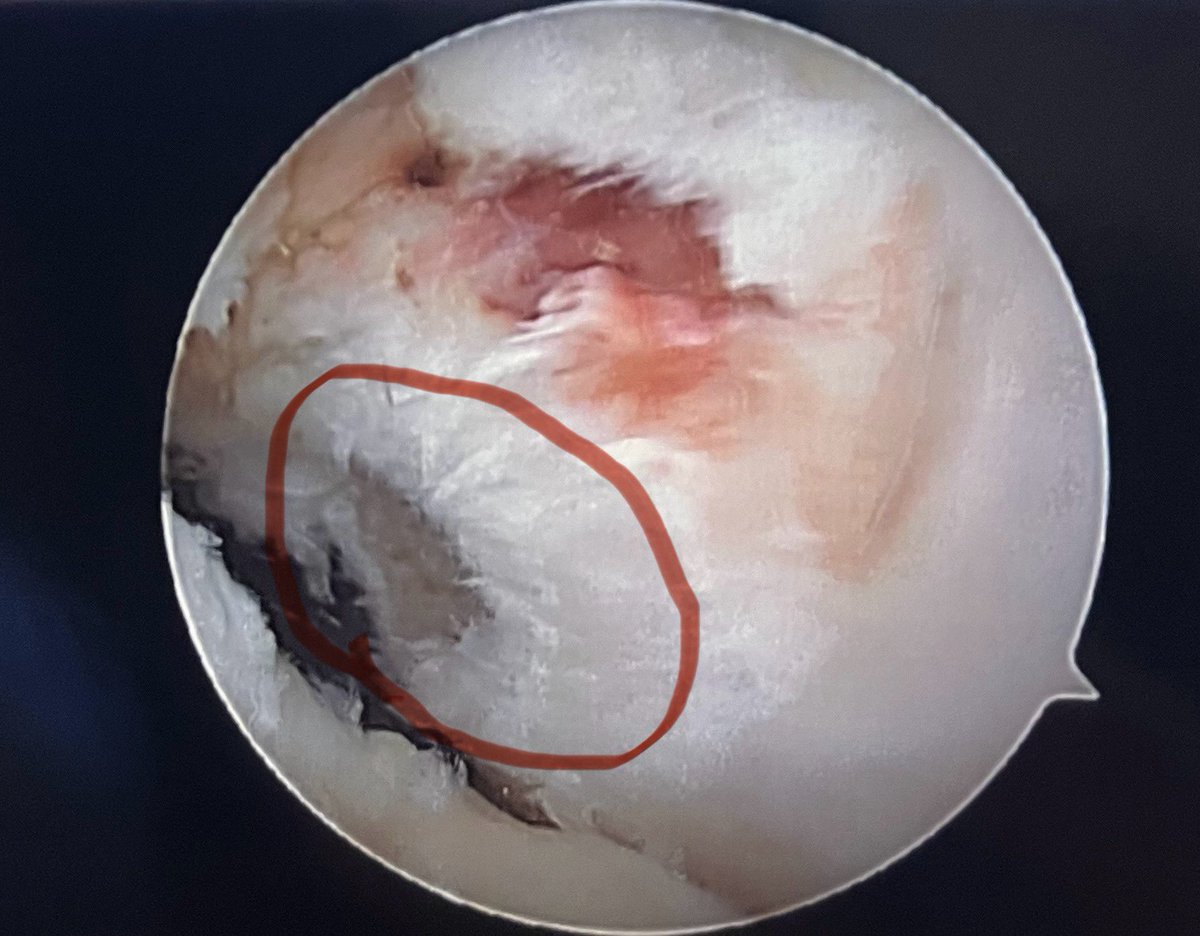

In many cases meniscocapsular separations are hidden unless you dislocate them, inside out set with our magic reuseable needle is a cost effective and can save your patient’s knee

#arthroscopy #savethemeniscus #sportinjuries